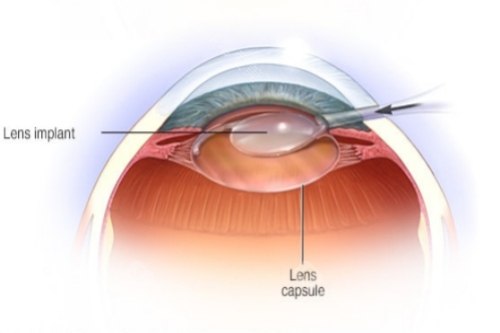

白内障正规开展了多种白内障手术,包括超声乳化白内障吸除术等,手术技术成熟,术后结果良好。

此外,科室还开展了一些潮流的眼科手术技术,如飞秒激光辅助白内障手术等,大大提高了手术的可靠性和有效性。